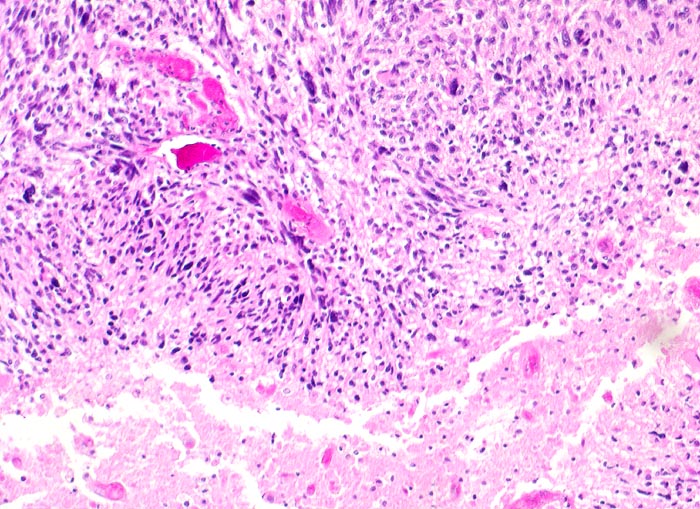

PathoPic – image database / PathoPic ID 5199 - Glioblastoma multiforme (WHO IV)

Glioblastoma multiforme (WHO IV)

maligner Tumor

Hirn temporal

Nervensystem

Histologie

100